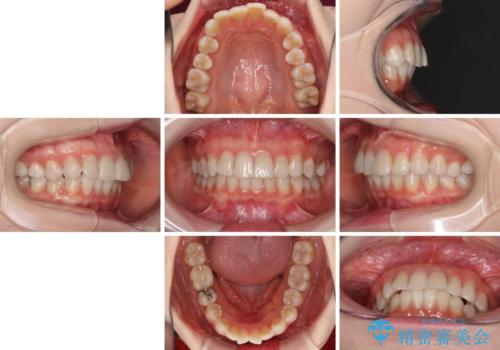

前歯の突出感とデコボコをインビザライン矯正で改善

- 上下前歯の突出感とデコボコを気にして来院された患者様です。

インビザラインによる上下歯列の側方拡大と後方移動、IPR(歯と歯の間を削る)にるスペースの獲得により歯列を整えることとしました。

骨格的な左右差があったため、上下の正中を合わせることができませんでした。

骨格の差は改善できないため、奥歯の咬み合わせに物足りなさを感じましたが、奥歯の咬み合わせによる不自由はなく、口元の突出感も改善することができました。